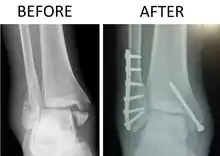

X-ray of trimalleolar fracture repair before and after ORIF surgery

A trimalleolar fracture is a fracture of the ankle that involves the lateral malleolus, the medial malleolus, and the distal posterior aspect of the tibia, which can be termed the posterior malleolus. The trauma is sometimes accompanied by ligament damage and dislocation.[1]

Surgical repair using open reduction and internal fixation is generally required, and because there is no lateral restraint of the foot, the ankle cannot bear any weight while the bone knits. This typically takes six weeks in an otherwise healthy person, but can take as much as twelve weeks. Non-surgical treatment may sometimes be considered in cases where the patient has significant health problems or where the risk of surgery may be too great.[1]